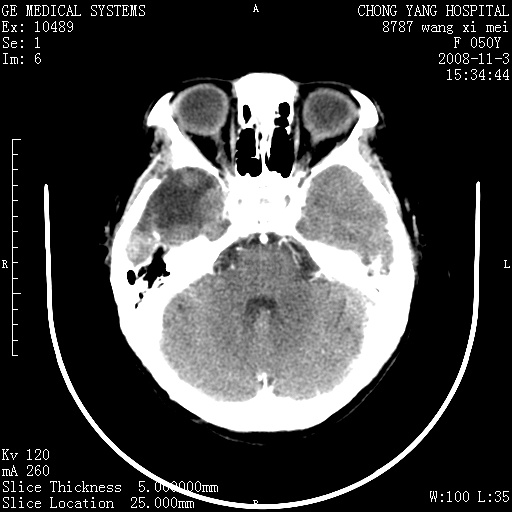

标题: CT16469:女,50岁,胶质瘤术后6年,今平扫加增强,请大家帮 [打印本页]

标题: CT16469:女,50岁,胶质瘤术后6年,今平扫加增强,请大家帮

右侧颞顶部可见低密度实变影,内见不规则钙化灶,边界不清,占位效应明显,侧脑室后角受压移位,符合胶质瘤术后复发改变。

右颞骨局限性缺如,局部脑组织无外隆。右颞叶可见片状脑脊液样低密度影,边缘较清,右侧侧脑室三角区可见一块状等密度影,且伴有强化,余未见明显异常改变。

考虑:右大脑术后改变伴肿瘤复发。

手术后局部片状低密度改变(软化灶),其后方颞叶似等密度病灶,界限不清,内见钙化,有轻度占位效应,但增强后强化之血管走行如常。应不考虑:复发!